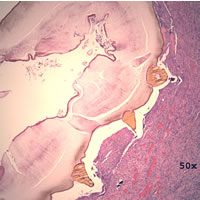

Case

98:

A 5-year-old girl developed an earache after vacationing in Belize with

her parents. A few months after returning from the vacation, her

parents took her to a New York City hospital for the earache where a biopsy

specimen was taken from her left ear. Her parents reported that

she had gone swimming during the trip. The following images

are from H & E (hematoxylin and eosin) stained sections of the biopsy. What

is your diagnosis? Based on what criteria?